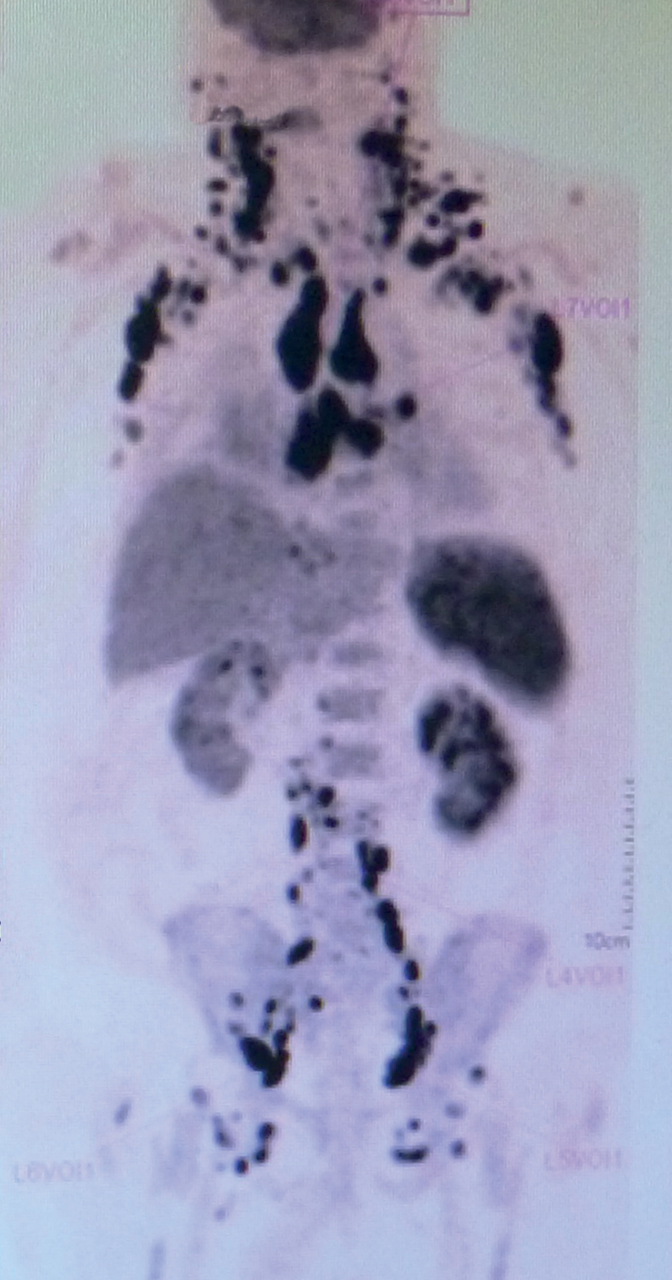

Un homme de 73 ans est hospitalisé pour une altération de l’état général avec une perte de poids de 10 kg en un mois.

L’examen clinique montre des adénopathies dans toutes les aires ganglionnaires.

Une tomodensitométrie à émission de positons (TEP) est réalisée.

Quel est votre diagnostic ?

La biopsie ganglionnaire objective un lymphome non hodgkinien de haut grade de type plasmablastique.